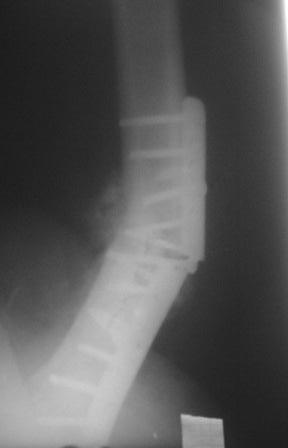

Обратился больной 54г. Травму получил в ноябре 2007г. Оперирован в Алмате (Казахстан). Через 2 мес. гипс снят, потом еще гипс на 2 месяц, с тех пор ходит двумя костылями, последние время беспокоит усиливающаяся боль и деформация.

Локально: укорочение ноги на 3,5см, умеренная отечность и вальгусная деформация, умеренная болезненность, патологической подвижности почти не определяется, но имеется наружная ротация конечности на 15гр.

Наш план БИОС, но так как при удалении пластини зона ложного сустава открывается, для уверенности производить костную пластику (аутографт или хотя-бы по Хахутову) ??, еще как устранить ротацию?

Уважаемый коллега! На мой взгляд необходимо удалить металлоконструкции, затем провести вскрытие костно-мозговых каналов, декортикацию и фиксация широкой пластиной LCP` 4,5\5,0.

Удалите винты и пластину из минидоступов, тогда зона ложного сустава не будет вскрыта.

Сегодня больного оперировал.Удаление пластины минидоступом не получилось , т.к. было еше 4 шурупа введенные под разными углами,

они были замурованы к/тканями. Наложено дистракционное устройство по методу А.Н. Челнокова, ротация и угловая деформация устранены, но оказалось в т/б суставе ограничены приведение и внутренная ротация, поэтому пришлось больного укладывать на бок, и с очень большим трудом произведены рассверливание и антеградное введение